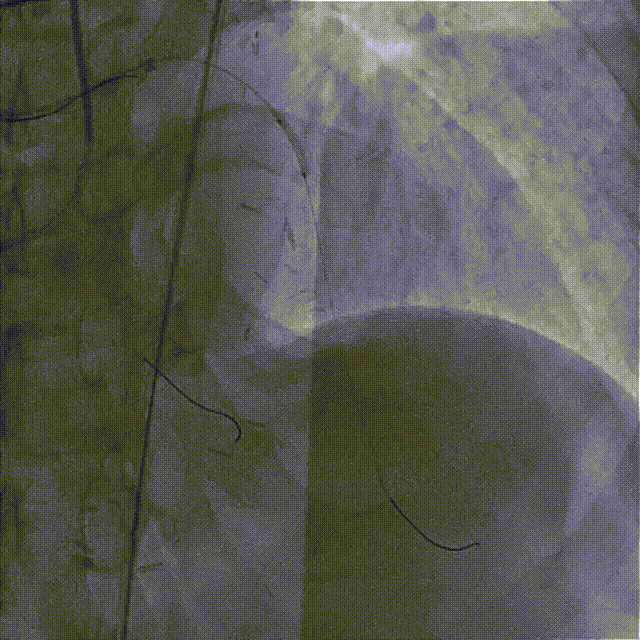

IVUS检查示:可见导丝全程走行与血管真腔,近中段重度纤维增生斑块伴局部钙化,远段血管床废用性萎缩。

于LAD病变处由远及近依次植入XIENCE Alpine 2.5mm x 18mm和XIENCE Alpine 3.0mm x 23mm支架各一枚。

造影示支架定位良好,D1开口受压90%狭窄,交换一根SION导丝穿支架网眼至D1远段,用Pinoeer1.5mm x 15mm、Pinoeer 2.0mm x 15mm球囊至D1开口处扩张。

FOXTROT NC 2.5mm x 15mm、FOXTROT 3.0 mm x 15mm后扩球囊后扩球囊至支架内后扩,以实现支架的充分贴壁,并对LAD远段进行球囊扩张,造影显示TIMI血流III级。

术后行IVUS检查示:支架定位贴壁扩张良好,LAD开口MSA:7.43mm2。